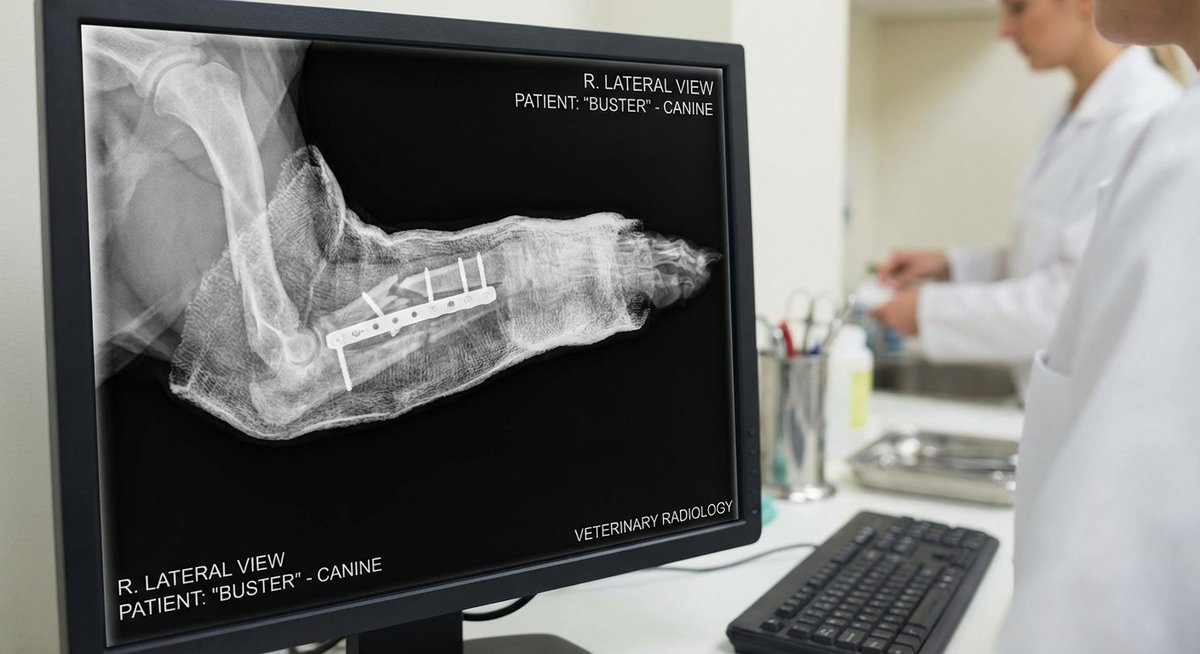

Die Behandlung hängt von der Art und Schwere des Bruchs ab. Dein Tierarzt wird zunächst ein Röntgenbild anfertigen, um die Fraktur genau zu beurteilen.

Bei komplexen Brüchen ist eine Operation die bessere Wahl. Der Chirurg fixiert die Knochenenden mit speziellen Implantaten.

| Plattenosteosynthese | Metallplatte mit Schrauben | Lange Röhrenknochen |